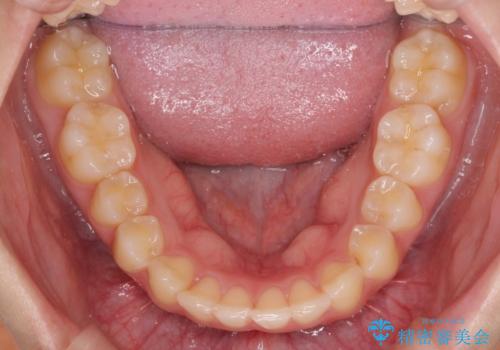

- 突出感のある、前歯の矯正治療を求めて来院されました。

軽度な突出・ガタつきを26枚・約半年の矯正治療期間で計画するインビザラインモデレートプランで治療を始めて行きます。

約半年といった短期間で、前歯の角度やガタつきを改善することができました。